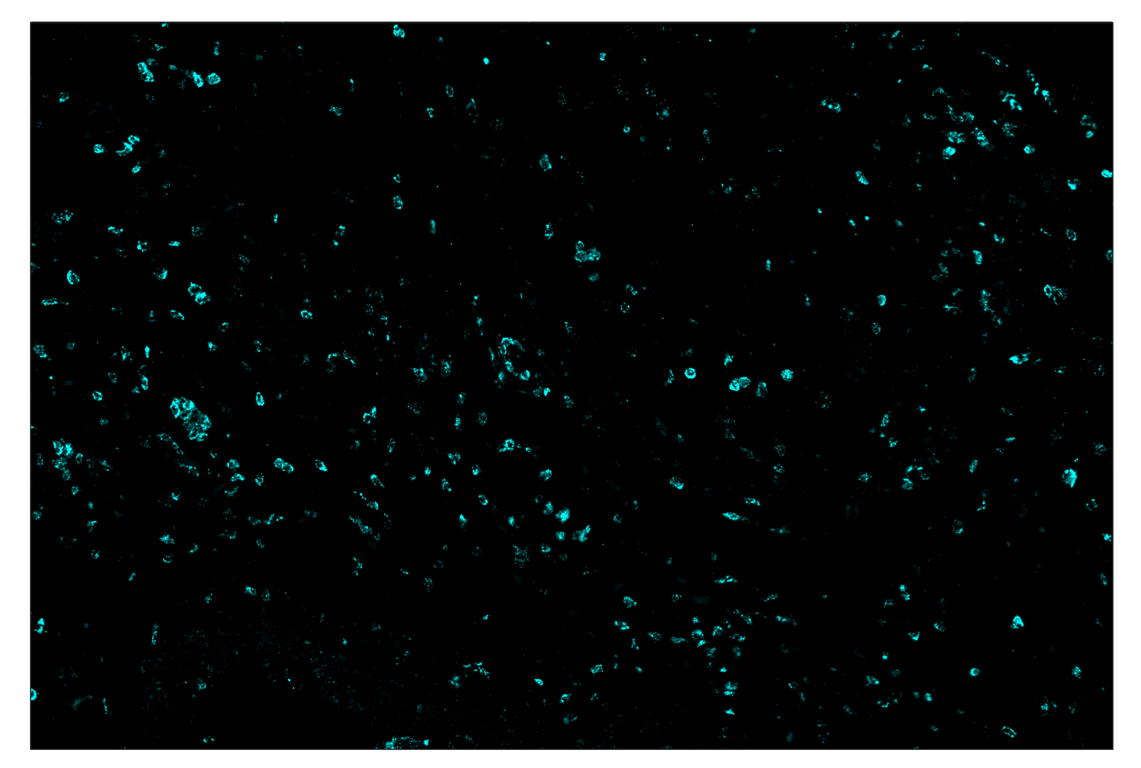

Immunohistochemistry Image 2: Myeloperoxidase (E1E7I) & CO-0138-750 SignalStar<sup>™</sup> Oligo-Antibody Pair

SignalStar™ multiplex immunohistochemical analysis of paraffin-embedded human colon adenocarcinoma using Myeloperoxidase (E1E7I) & CO-0138-594 SignalStar™ Oligo-Antibody Pair #39503 (yellow). All fluorophores have been assigned a pseudocolor, as indicated. Staining was performed on the BOND RX autostainer by Leica Biosystems.